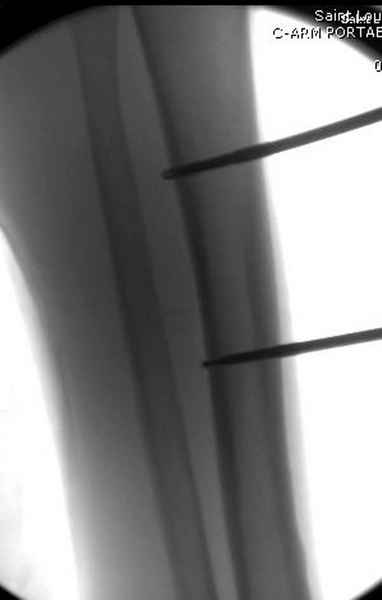

Больному с политравмой установлен наружный "spanning-bridging" фиксатор, после нескольких Irrigation&Debridment на фоне отрицательного посева из раны, через открытый участок установлен 4.5 mm Locking Plate.

Имя     : 4 tibia exfix 2 a.jpg

Тип     : image/jpeg

Размер  : 18013 байтов